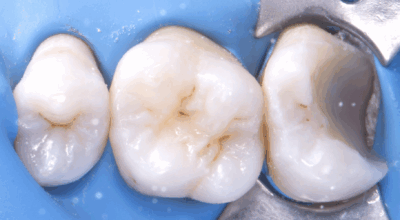

Cas clinique

Coiffage pulpaire direct : 90,4% de taux de succès